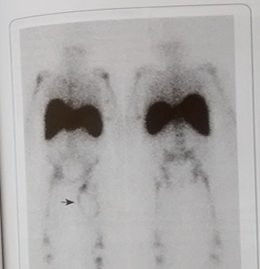

Sistema Hematopoyético

Cartera de servicios a nivel de estudios y exámenes especializados del sistema hematopoyético.